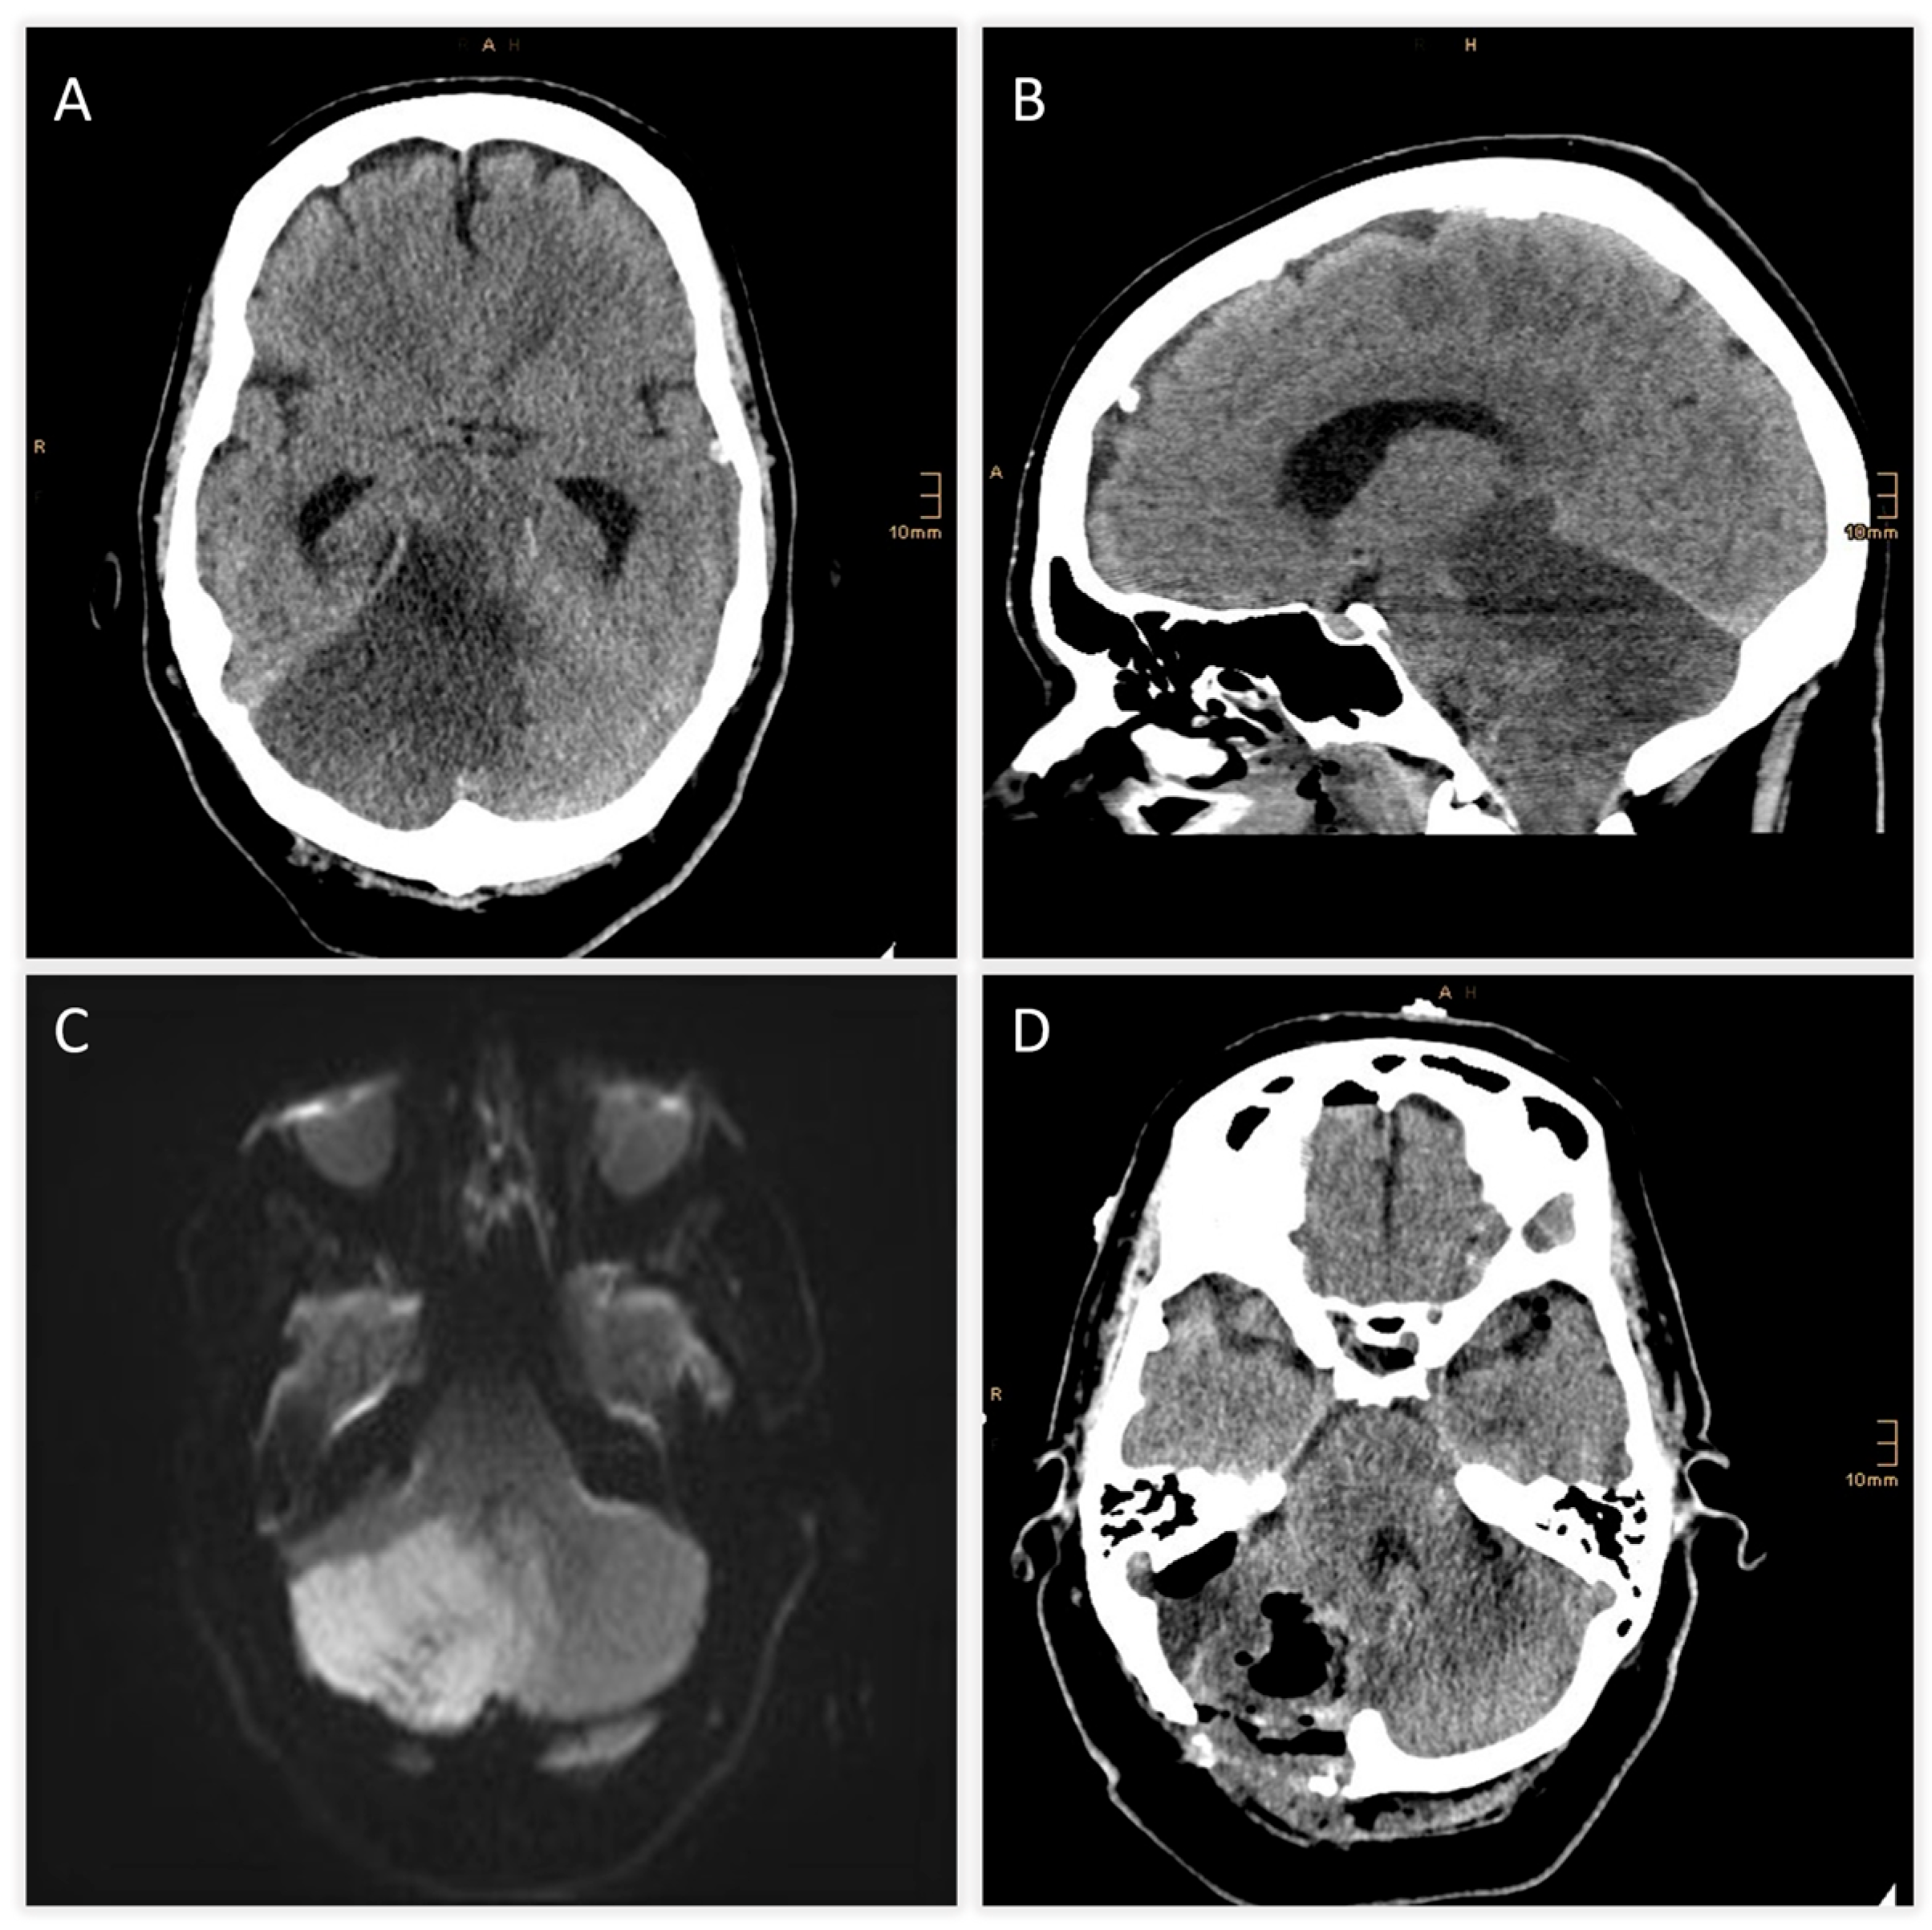

| +6 h | CT scan | Expanding right cerebellar infarct with mass effect; apparent hypodensity in pons, midbrain, diencephalon → suspicious for brainstem infarction |

| +7 h | MRI follow-up | Brainstem infarction excluded; predominant cerebellar edema confirmed |

| +8 h | Neurosurgical intervention | Suboccipital decompression, ventricular drainage, and partial resection of necrotic tissue |